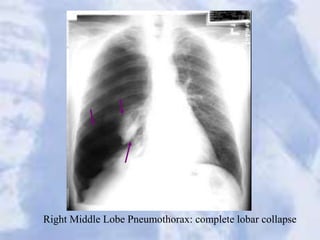

Right Middle Lobe Pneumothorax: complete lobar collapse

Post chest tube insertion and re-expansion

Right Middle LobePneumothorax: complete lobar collapse

Post chest tubeinsertion and re-expansion